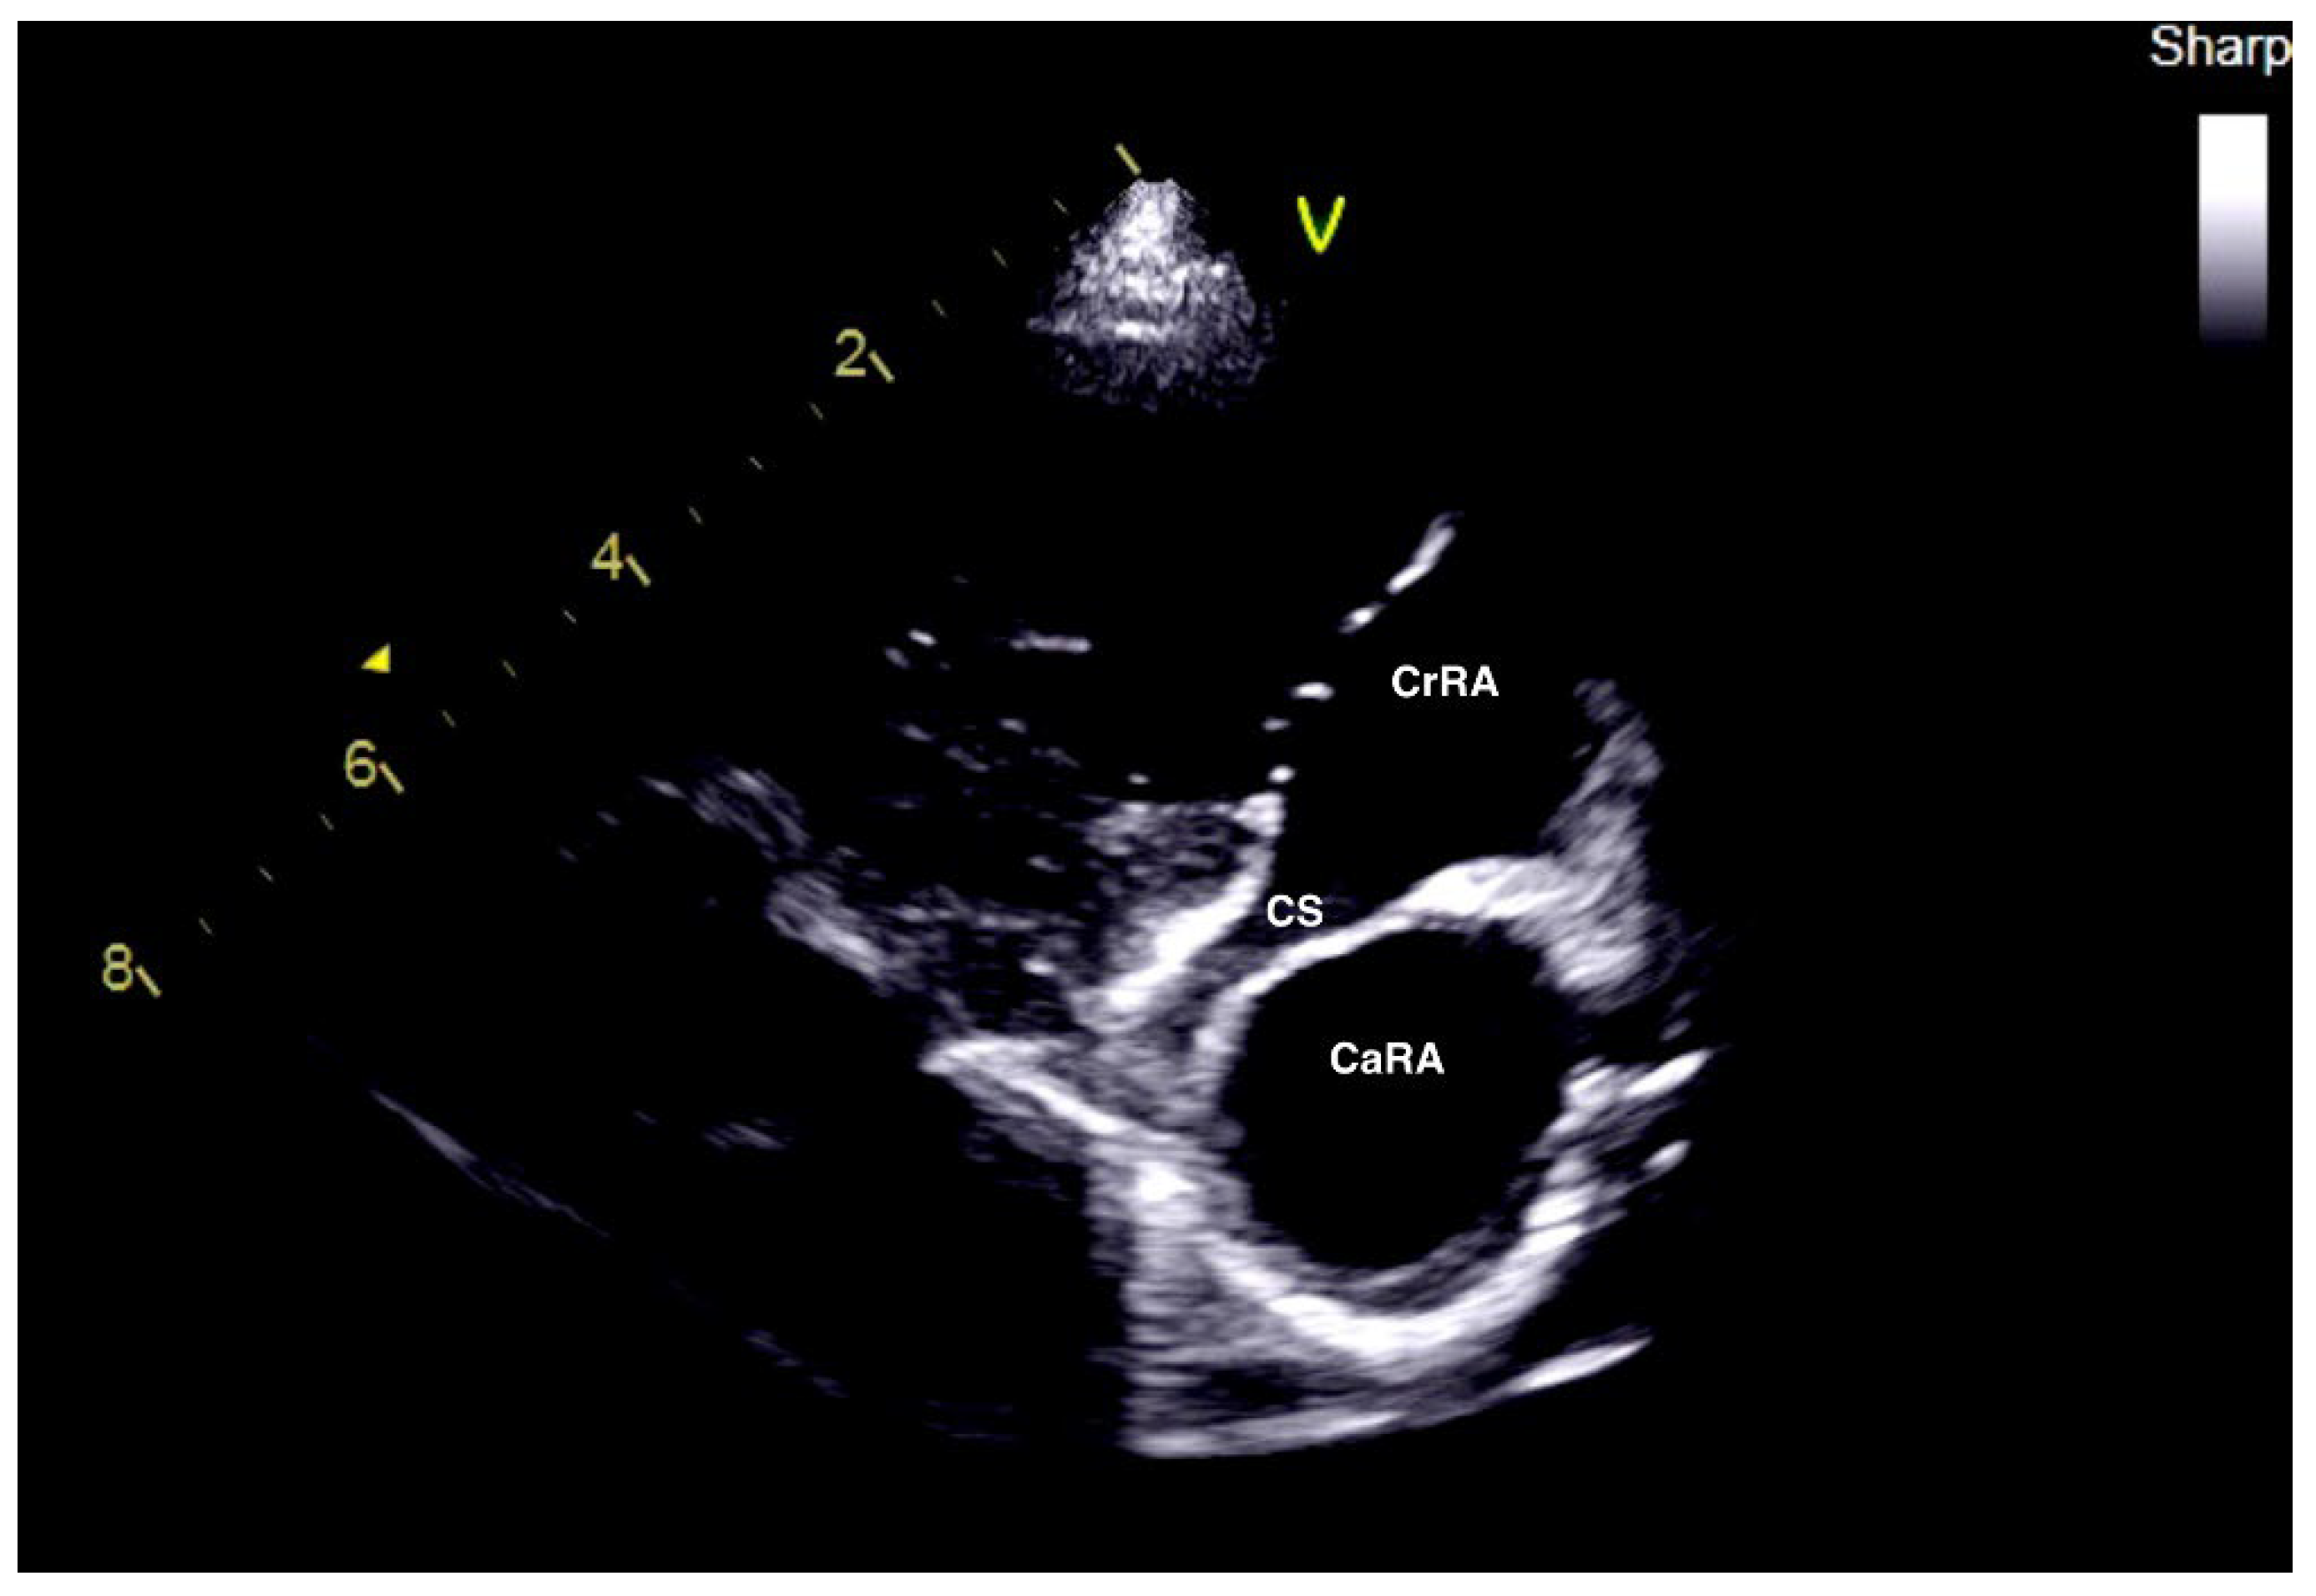

2.1. Case 1

2.2. Case 2